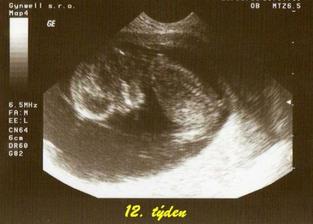

tak tohle album obsahuje vše co se týká našeho prvního miminka, které nosím pod svým srdíčkem, výbavičky co chystáme a co bychom chtěly nachystat.. Narodit se má 6.3.2009 , nevíme co to bude - asi necháme jako překvapení.